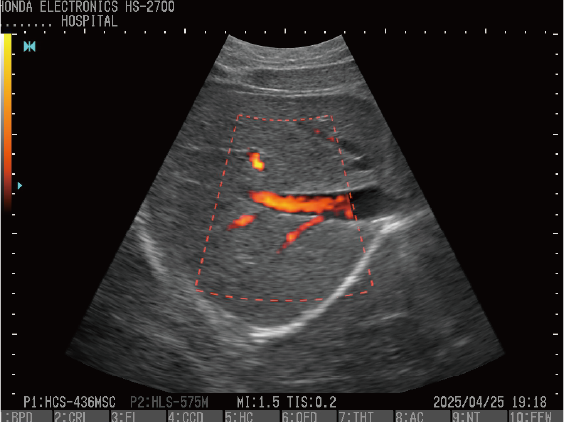

CFM(カラーフローマッピング)

プローブ:HLS-575M

プローブ:HCS-436MSC